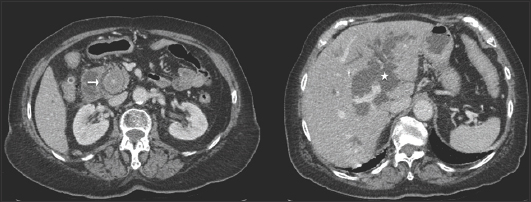

An 86-year-old patient known for recurrent symptomatic cholelithiasis episodes and previous cholecystectomy presented to the emergency department for epigastric pain, fever, dark urine, and clear stools. Physical examination revealed jaundice and right upper quadrant tenderness without guarding. Laboratory results showed moderate inflammatory syndrome and increased total bilirubin level (165 µmol/L, N: <17 µmol/L) with cholestasis and hepatic cytolysis. Lipase was normal. Computed tomography scan showed a 3.7-cm choledocholithiasis (Fig. 1, arrow) with extra- and intrahepatic bile duct dilatation (Fig. 1, asterisk).

Figure 1 Computed tomography scan: axial slices showing a large calculus in the common bile duct (arrow) and dilatation of the extrahepatic and intrahepatic (asterisk) bile ducts